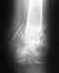

Re: Перелом плечевой кости

послал Alexander Chelnokov 10 Ноябрь 2016, 02:13

Сделано все неплохо.